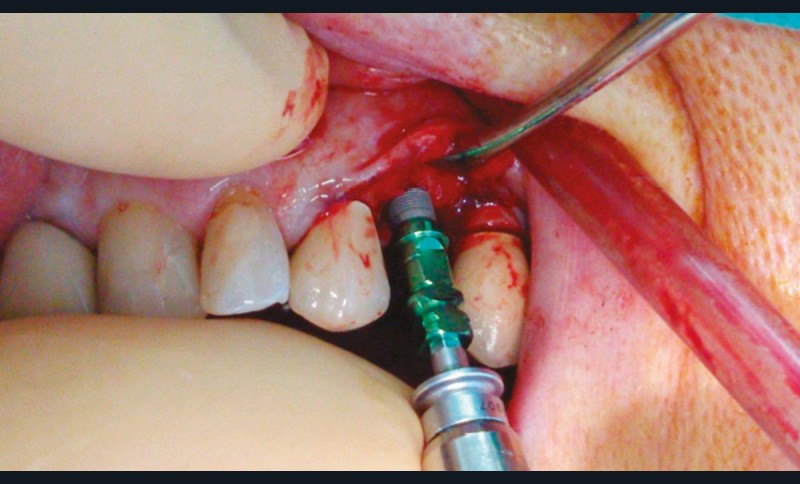

Un contrôle à la fréquence de 4 à 6 mois devra être instauré. La fréquence sera adaptée à l’état bucco-dentaire et à l’appréciation des facteurs locaux de susceptibilité du patient (risque carieux, biotype parodontal). La motivation à l’hygiène et l’efficacité du contrôle de plaque devront être entretenues. Les soins conservateurs précoces seront bien entendu privilégiés. Dans ce contexte, il ne faudra pas hésiter à conserver des dents d’une valeur intrinsèque faible pour éviter le recours à un geste chirurgical. En cas de carie délabrante ou de mobilité modérée, les soins conservateurs devront être privilégiés (endodontie, contentions). En cas d’infection, un traitement conservateur devra également être envisagé (fig. 2).

La priorité devra être donnée à la suppression de la composante infectieuse. Ainsi, pour éviter une extraction, il pourra être légitime de préconiser la conservation d’une dent à l’état de racine sur laquelle le traitement endodontique aura permis la stérilisation du foyer infectieux. Cependant, ce traitement conservateur ne sera retenu qu’à condition de pouvoir conserver durablement cette racine par une obturation étanche à l’aide d’un matériau de reconstitution définitif. Toutefois, pour contrôler l’infection, l’extraction pourra être nécessaire d’emblée ou en cas d’échec d’un traitement conservateur.